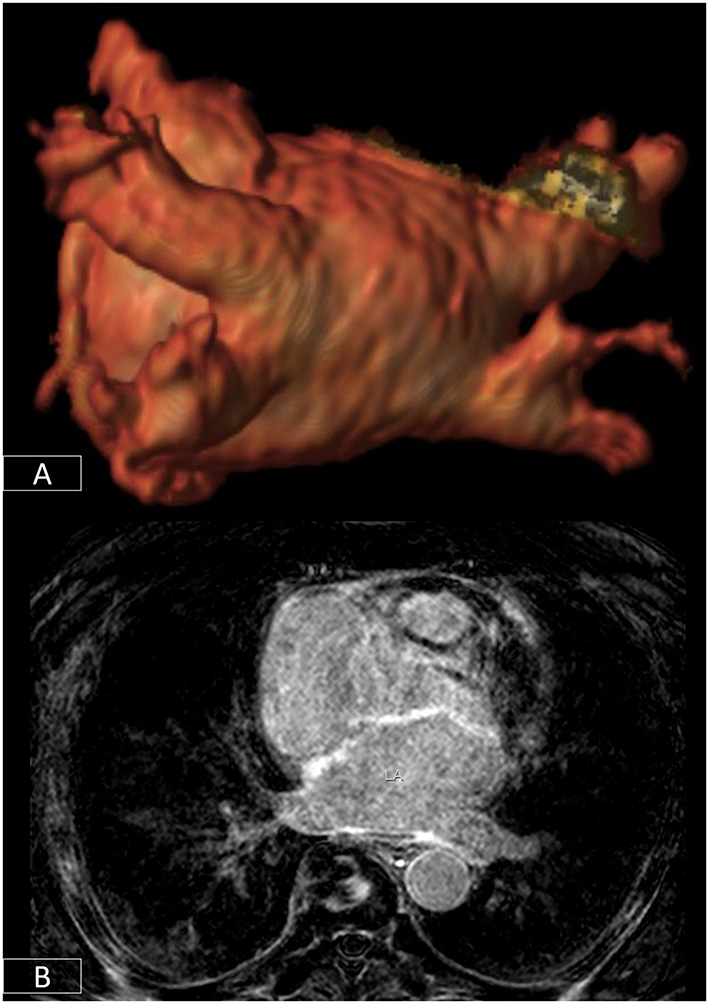

Figure 6

3D-segmentation of the left atrium depicting left atrial anatomy and four pulmonary veins and their tributaries (A). There is extensive fibrosis of the left atrial wall (B) on 3D late enhancement sequences which may reduce the likelihood of successful ablation.